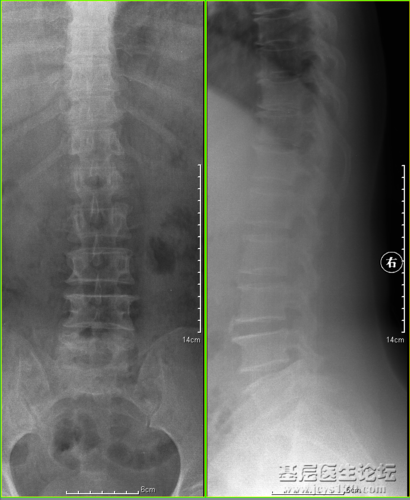

腰5楔型变 写美篇 x线片显示:腰5楔型变,腰椎侧弯,腰椎明显骨质增生

腰椎骨质增生.png

患儿董xⅩ,女,77岁,胸12,腰1椎体压缩性距骨骨折,腰椎骨质增生.